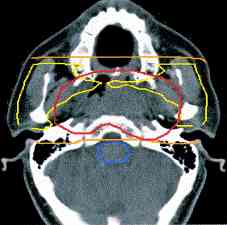

radiation isodose #1 , #2, #3, #4, #5 |